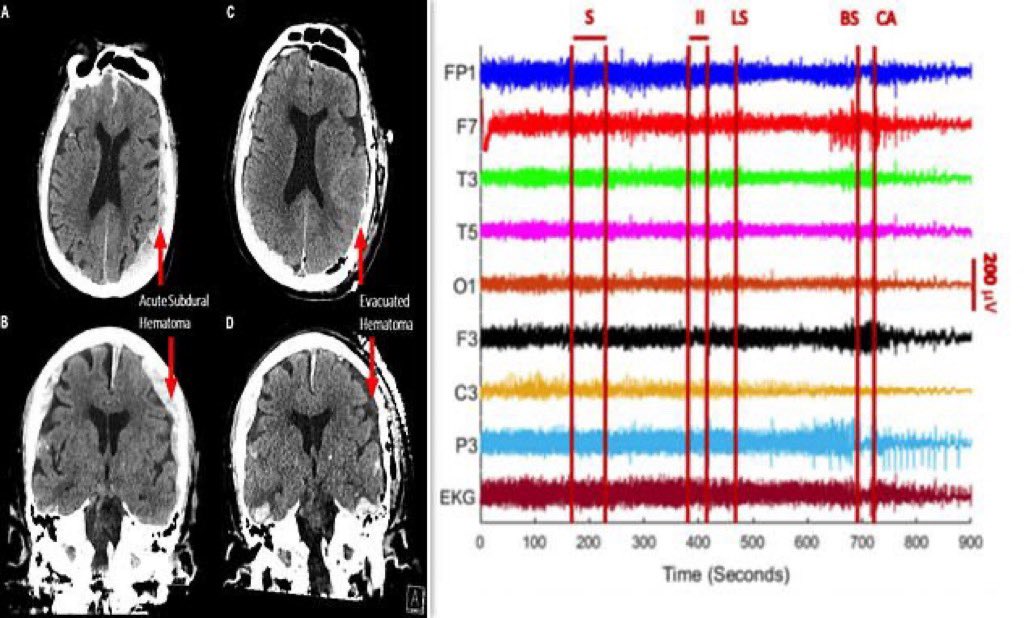

قام العلماء لاول مرة بتسجيل نشاط الدماغ الإنسان عند وفاته حيث أجريت لمريض كبير بالسن عمره87 ومصاب بمرض الصرع،قاموا بوضع جهاز تخطيط كهربائي وسجلوا نشاط الدماغ لمدة 15دقيقة،واكتشفوا العلماء شي غريب وعلموا من خلاله ماذا يشاهد الانسان عند حضور أجله.

لاحظوا العلماء ان نشاط كبير بموجات غاما بالدماغ والتي ترتبط بعمليات مثل الحلم والتأمل واسترجاع الذاكرة اي بمعنى ان الانسان يشاهد شريط حياته بشكل كامل قبل رحيله وتكون بعملية تسمى استدعاء الحياة،ونلاحظ ان الاشخاص الذين تتوقف قلوبهم يشاهدون اشياء غريبة من كائنات يشع منه النور.